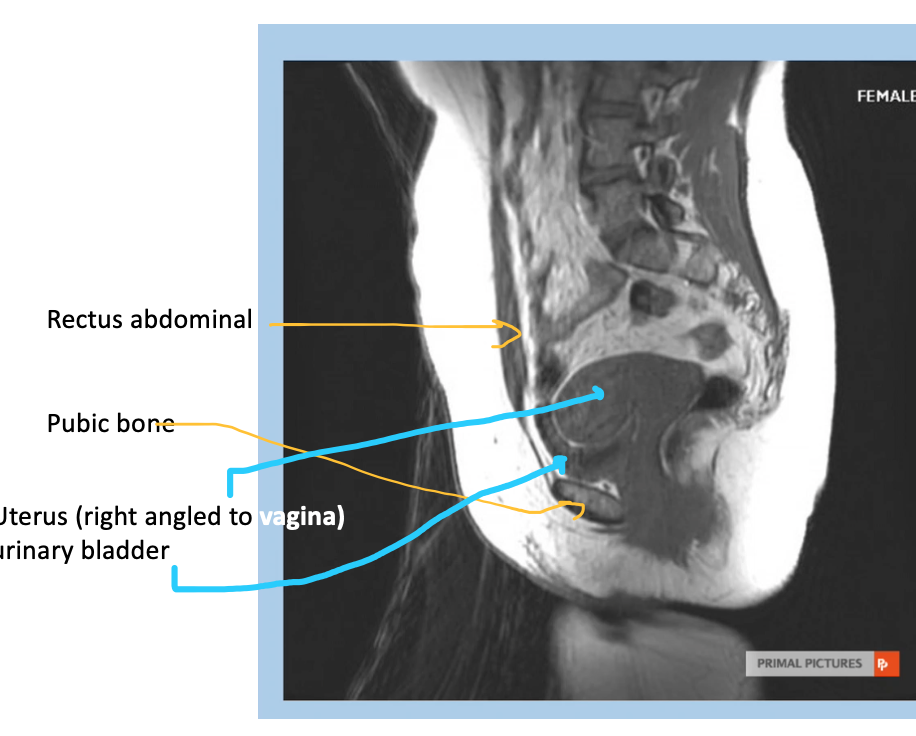

What type of imaging modality is this & fill in the blanks

MRI prostate, axial